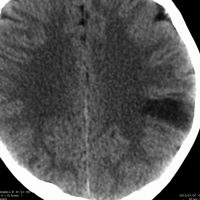

3歳で最初のてんかんらしいと言われる発作があり,その後は発作は見えず自動症と診断され徐々に学習能力の低下が認められ,7歳の時に外来を訪れました。週に3回くらい腹痛や嘔気があってすぐに眠くなってしまう。耳鳴がすごくてしばらく何も聞こえなくなってしまう,話も理解できなくなるなど,側頭葉てんかんの特徴をたくさんエピソードとして持っていましたが,症候性てんかんとは診断されませでした。側頭葉にどのような機能があるのかを証明してくれる症例でもあります。

典型的なDNTの画像で説明するまでもありません。ガドリニウムでは全く増強されませんでした。左上側頭回と角回の境界域に存在します。

側脳室壁のあたりまで全摘出しました。とても柔らかい腫瘍で吸引できました。